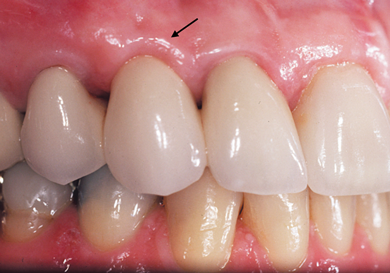

A patient presented with two defective 3-unit fixed partial dentures spanning teeth Nos. 6 through 8 and teeth Nos. 9 through 11 (Figure 7). The defective fixed partial dentures were removed (Figure 8), an impression was made, and traditional provisional fixed partial dentures without ovate pontics were placed. After the impression was sent to the laboratory, the lab technician prepared ovate pontic sites on the stone cast (Figure 9) and fabricated the new definitive bridges. On the day of insertion, the provisional fixed partial dentures were removed (Figure 10), ovate pontic sites were prepared using a teardrop-shaped diamond bur (Figure 11), and the sites were sounded to confirm that there was at least 2 mm from the base of the pontic site to the alveolar bone (Figure 12). The fixed partial dentures were cemented, and the postoperative healing was uneventful (Figure 13).

(10.) Close-up view of the existing edentulous tooth No. 10 site prior to the creation of the ovate pontic site.

Figure 10

(11.) Close-up view of the preparation of the ovate pontic sites.

Figure 11

(12.) Bone sounding was performed to confirm that there was at least 2 mm from the base of the pontic sites to the alveolar bone.

Figure 12

(13.) Close-up retracted 2-month postoperative view of the final fixed partial dentures spanning teeth Nos. 6 through 8 and teeth Nos. 9 through 11, along with replacement crowns for the other restored maxillary teeth.

Figure 13